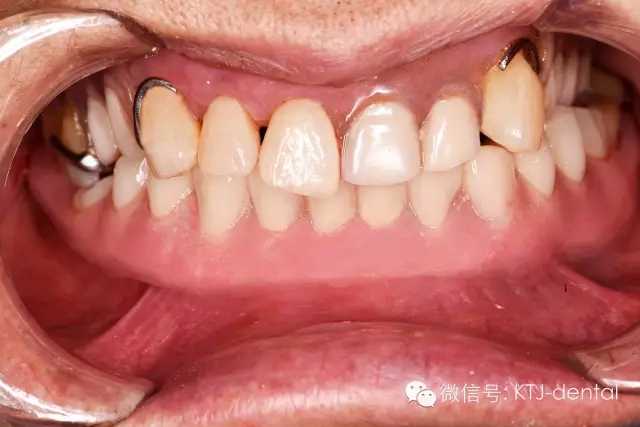

1術(shù)前全口正面照

圖1 患者多牙缺失,牙周情況欠佳

4即刻種植即刻修復(fù)的最終,全口正面照

本病案小結(jié):使用預(yù)成種植套筒冠基臺行無牙合即刻負重手術(shù)操作簡單,效果可靠,臨床應(yīng)用方便快捷。但種植體的平行度是保證此修復(fù)方式成功實施的關(guān)鍵。本病例的CAD CAM手術(shù)導(dǎo)板在應(yīng)用過程中發(fā)揮以下作用:嚴格控制種植體的平行度,避免損傷下牙槽神經(jīng)及頦神經(jīng)(無須翻瓣暴露神經(jīng)),根據(jù)種植體植入深度預(yù)選適當(dāng)?shù)幕_,根據(jù)術(shù)前打印模型預(yù)先調(diào)磨即刻負重義齒。CAD CAM手術(shù)導(dǎo)板的應(yīng)用使得手術(shù)操作有更強的預(yù)期性。在應(yīng)用技巧方面,預(yù)先保留不影響植入位點的牙齒,獲得更為精確的牙支持式的手術(shù)導(dǎo)板,減少了手術(shù)誤差。半程導(dǎo)板配套的器械盒應(yīng)該合理地與相應(yīng)種植系統(tǒng)外科器械配合使用,并根據(jù)骨的質(zhì)地采用相應(yīng)的預(yù)備方式,使得植入位點精確,并獲得良好的初期穩(wěn)定性完成下一步的即刻負重治療。